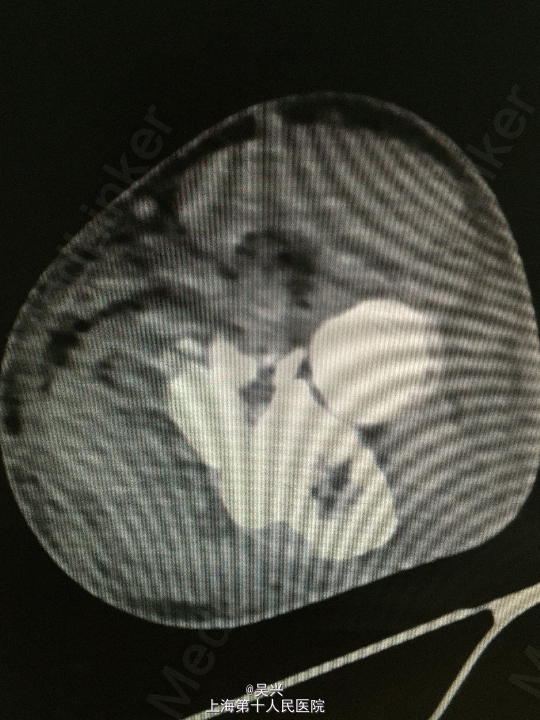

左肘外伤肿痛畸形3小时。左肘屈曲位着地受伤。

急症查体见肘关节肿胀、触痛,存在向后方半脱位及外侧松弛不稳定。

诊断:左肘恐怖三联症。 处理:术前准备,抗炎消肿治疗,术后三天行左肘正中切口显露尺骨冠状突,术中见尺骨冠状突粉碎性骨折,用两枚微型空心螺钉固定,发现屈肘位置仍有肘关节半脱位趋向。予伸肘位石膏固定,术后2周改屈肘45度位石膏固定,术后4周拆石膏,能逐渐屈肘至90度。

随访:术后1月患者肘关节稳定性良好,伸肘0度,屈肘90度,理疗辅助功能锻炼中。 讨论:肘关节脱位(半脱位)伴尺骨冠状突骨折、桡骨小头骨折称为肘关节恐怖三联症。该症存在极度肘关节不稳定,容易发生向后方、侧方脱位。一般单纯尺骨冠状突骨折极少,多伴有桡侧结构损伤和关节不稳定。肘关节恐怖三联症治疗原则一般是复位固定尺骨冠状突和桡骨小头,修复桡侧副韧带。我们术中发现固定尺骨冠状突后关节仍然不稳定,但桡骨小头因不全骨折需要石膏固定,因此不采取手术修复外侧副韧带,而是石膏固定,术后也取得较好的效果。